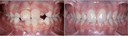

Il Dr. Giuseppe Manti è un dentista di fiducia a Messina, specializzato in ortodonzia e odontoiatria pediatrica. Grazie all'utilizzo di tecnologie all'avanguardia, offre piani di cura personalizzati per ogni paziente, sia adulti che bambini. La clini...Vedi di più

| Ortodonzia | N/A |

| Ortodonzia pediatrica | N/A |